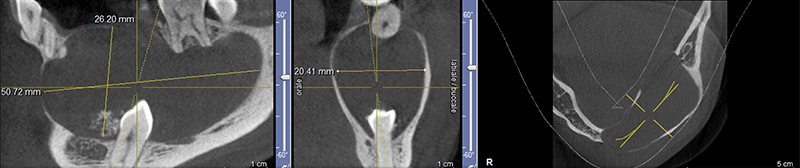

L’examen Cone Beam confirme le caractère monogéodique de la lésion, de dimension 51x26x20mm.

Celle-ci entraîne une déformation et un amincissement des corticales et s’insère au collet de la dent incluse.

La dent 34 refoulée au niveau du rebord basilaire, présente des images de résorption interne en feuillets et on retrouve des calcifications à son contact. Enfin, on met en évidence des images de résorption radiculaire externe sur les dents 43, 42, 41, 31, 32, 33, 35 et 36.

Fig. 02 : Cone Beam qui permet d’apprécier la taille, le refoulement des structures dentaires, l’effet de masse et l’amincissement des structures osseuses.